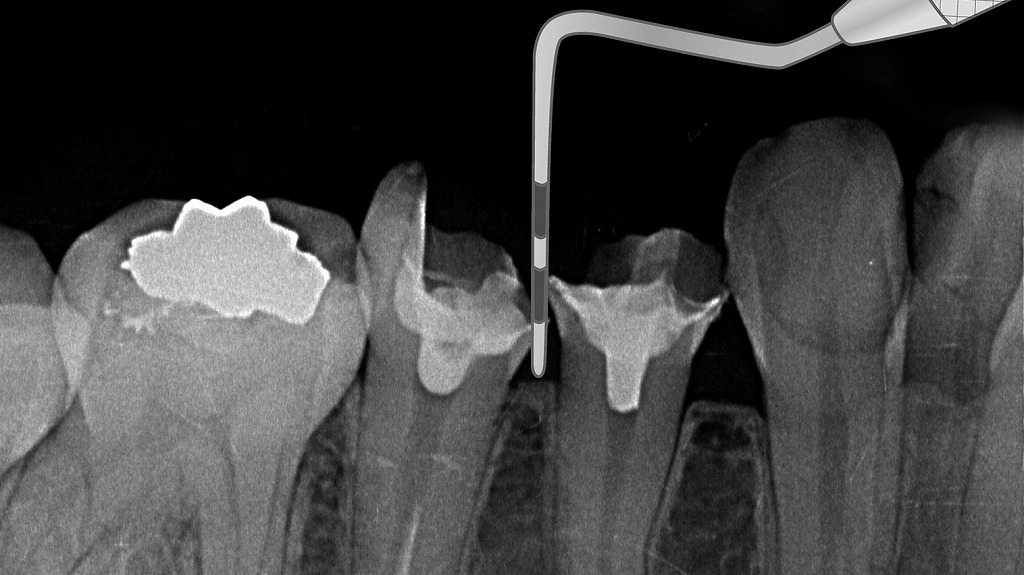

〈解説-浅いポケットで健康な歯周組織の状態〉

プローブを挿入しても、浅い位置(1〜3mm)で止まるのが確認できます。

X線でも、歯根を取り囲む骨がしっかりと存在し、歯槽骨の高さが正常に保たれています。

このように浅いポケットは、歯肉が引き締まり炎症の少ない健康な歯周組織の特徴です。